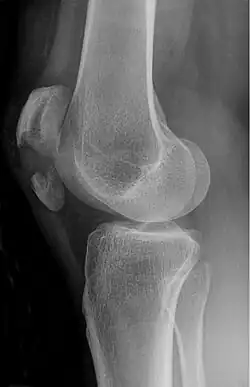

Osteochondral fracture of patella -

The patella can break in various ways depending on the way it is injured, and into two or more pieces.[1] Types include transverse, the most common, with one fracture line;[5] marginal; osteochondral; and the rare vertical type, or stellate, where a direct compression force gives rise to a comminuted pattern.[5][7] Patella fractures can be further classified as displaced, where the broken ends of bone do not line up correctly and separate by more than 2mm, or undisplaced and stable where pieces of bone remain in contact with each other.[1][7] If fragments of patella bone stick out from the skin it is known as an open patella fracture, and closed if the overlying skin is intact.[1]